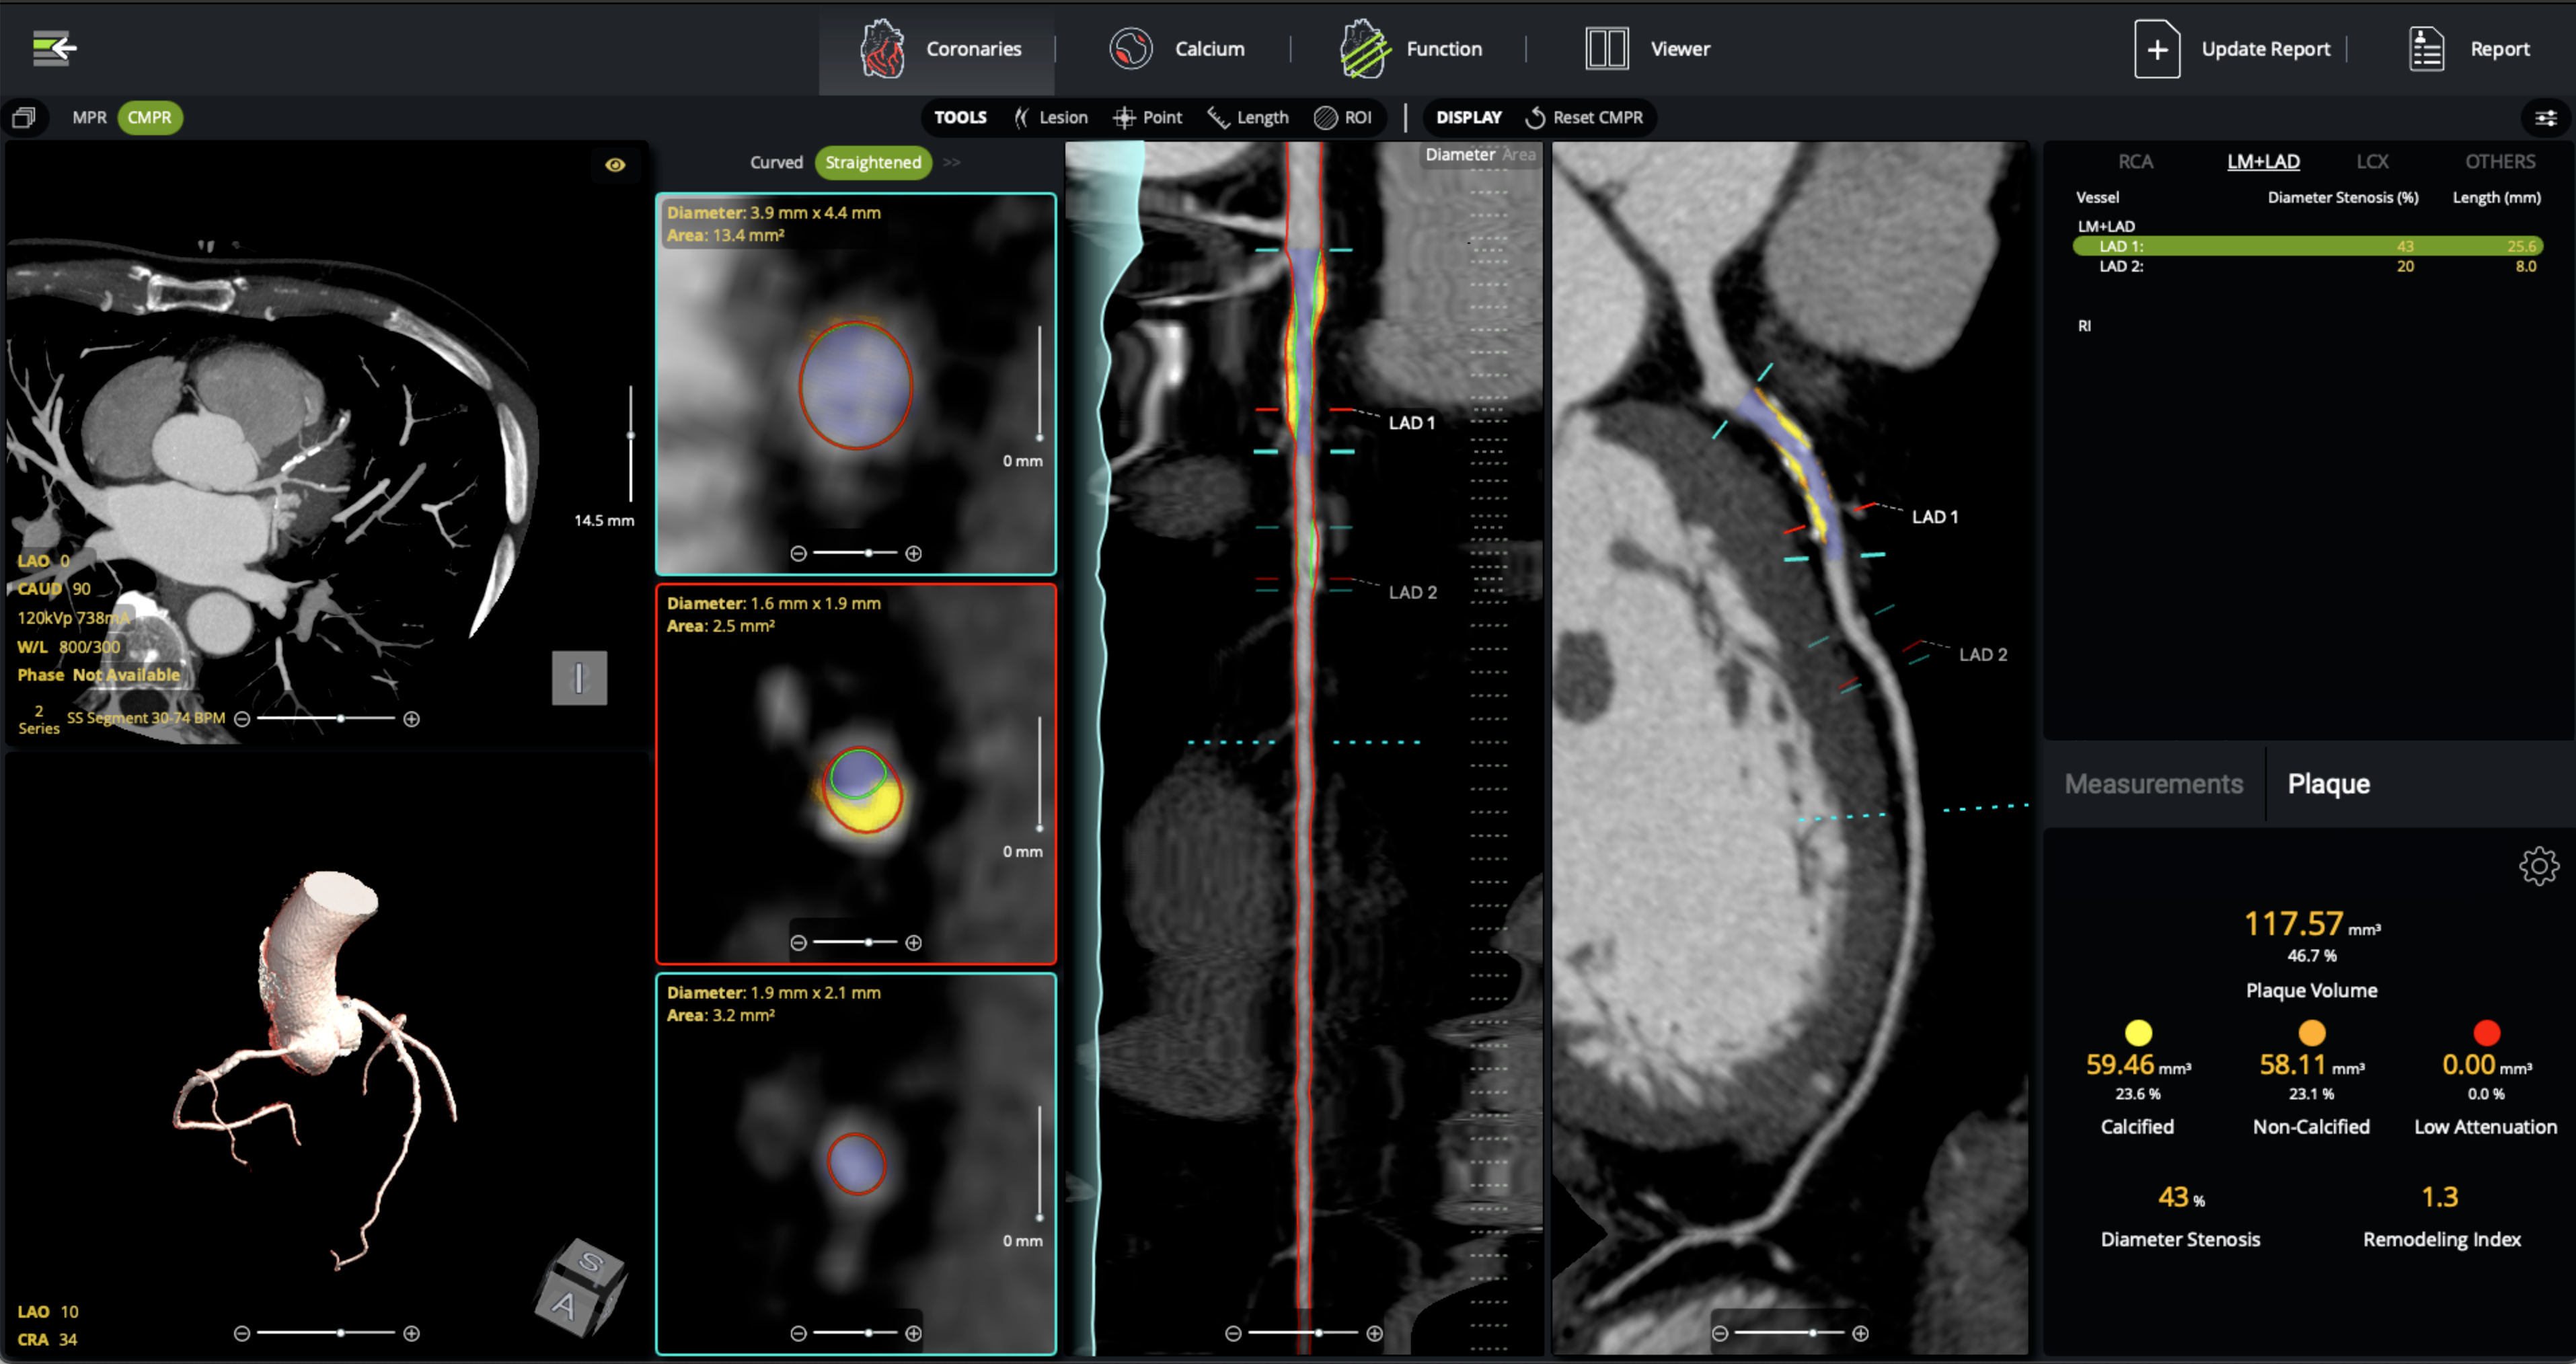

cvi42 | Plaque* empowers cardiac imaging teams with AI-enabled, on-premise quantification of atherosclerotic burden for clinical use. It delivers precise measurements of plaque volume, burden, composition, and distribution, all fully integrated into your CT workflow, without the need to send away to an outside reading service.

- Automated coronary lumen and wall segmentation ensures rapid, reproducible plaque quantification

- Per-lesion and per-vessel analysis provides detailed assessment of calcified, non-calcified, and low attenuation plaque for precise risk stratification

- Remodeling index calculation identifies high-risk plaques beyond stenosis severity